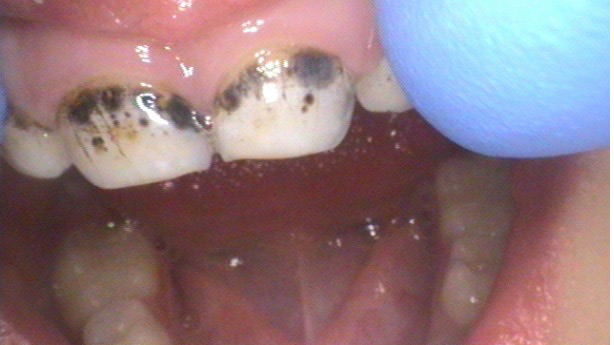

Use of “Black Magic” in arresting oral decay in Sjögren’s disease patients

Laing-thumbnail alternate text for this image

Sjögren’s Disease (SjD) is a systemic autoimmune disease characterized by lymphocytic infiltration and dysfunction of the exocrine glands, notably the lacrimal and salivary glands. The oral consequences include salivary gland dysfunction, altered salivary compositions, and loss of protective effects from saliva such as buffering capacity, antimicrobial capabilities, and clearance of bacteria and food debris.1 The disease … Read more